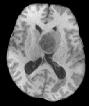

Machine learning has been widely adopted for medical image analysis in recent years given its promising performance in image segmentation and classification tasks. The success of machine learning, in particular supervised learning, depends on the availability of manually annotated datasets. For medical imaging applications, such annotated datasets are not easy to acquire, it takes a substantial amount of time and resource to curate an annotated medical image set. In this paper, we propose an efficient annotation framework for brain MR images that can suggest informative sample images for human experts to annotate. We evaluate the framework on two different brain image analysis tasks, namely brain tumour segmentation and whole brain segmentation. Experiments show that for brain tumour segmentation task on the BraTS 2019 dataset, training a segmentation model with only 7% suggestively annotated image samples can achieve a performance comparable to that of training on the full dataset. For whole brain segmentation on the MALC dataset, training with 42% suggestively annotated image samples can achieve a comparable performance to training on the full dataset. The proposed framework demonstrates a promising way to save manual annotation cost and improve data efficiency in medical imaging applications.

翻译:近年来,由于在图像分割和分类任务方面表现良好,医学图像分析广泛采用了机器学习。机器学习的成功,特别是监督学习的成功,取决于手动附加说明数据集的可用性。对于医疗成像应用来说,这种附加说明数据集不容易获得,需要大量的时间和资源来翻译附加说明的医学成像集。在本文件中,我们建议为大脑MR图像建立一个高效的注释框架,为人类专家提供信息性样图像,供人类专家作说明。我们评估了两种不同的大脑图像分析任务的框架,即脑肿瘤分割和整个大脑分割。实验显示,对于BRATS 2019数据集的脑肿瘤分割任务,培训一个只有7%的附加说明图像样本的分解模型,其性能与全数据集培训的性能相当。对于MALC数据集的整个大脑分割,用42%的附加说明性图像样本进行的培训,可以实现与全数据集培训的类似性能。拟议的框架展示了节省人工注解成本和提高医疗成像应用数据效率的有希望的方法。